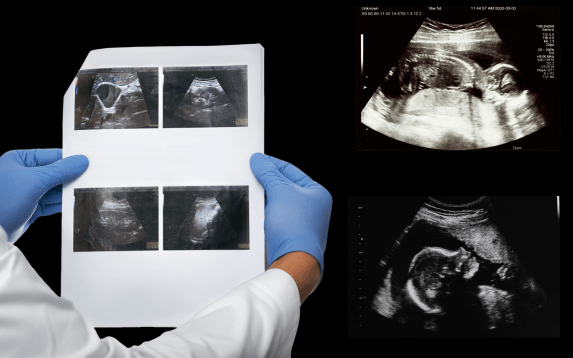

A genetic sonogram is an advanced ultrasound test that evaluates the baby’s risk for chromosomal or genetic conditions. It is usually done between 18 and 22 weeks of pregnancy. The scan helps doctors look for specific physical markers that may suggest chromosomal differences, such as Down syndrome or other genetic abnormalities. This safe and non-invasive test gives valuable insights into the baby’s overall health and development.

The main goal of a genetic sonogram is early detection. It helps identify markers that can guide further testing or genetic counseling if needed. When performed at the right time, this scan offers reassurance to parents and helps doctors plan any additional care required. Early awareness also supports better pregnancy management and preparation for possible medical needs.

The procedure is similar to a regular ultrasound. A transducer is gently moved over the mother’s abdomen to capture detailed images of the fetus. The sonographer checks the baby’s heart, brain, spine, and other organs. At Isha IVF Centre in Palanpur, our specialists use high-resolution ultrasound machines to ensure accurate results while maintaining comfort and safety throughout the scan.

A genetic sonogram can detect subtle signs that standard ultrasounds may miss. It plays a key role when combined with blood tests or other genetic screenings. Together, they help confirm whether a baby has an increased risk of genetic conditions. At Isha IVF, we use this combined approach to give parents a clearer understanding of their baby’s health.

At Isha IVF in Palanpur, every genetic sonogram is performed by experienced fetal medicine experts. We combine advanced imaging technology with professional care to ensure precise evaluation. Our team explains every finding in simple language so parents can make informed choices with confidence.

Choosing a genetic sonogram at Isha IVF means taking an important step toward safe pregnancy monitoring. With timely diagnosis, expert interpretation, and compassionate guidance, we help expectant parents prepare for a healthy journey ahead. Our focus is always on early detection, emotional support, and accurate care for both mother and baby.